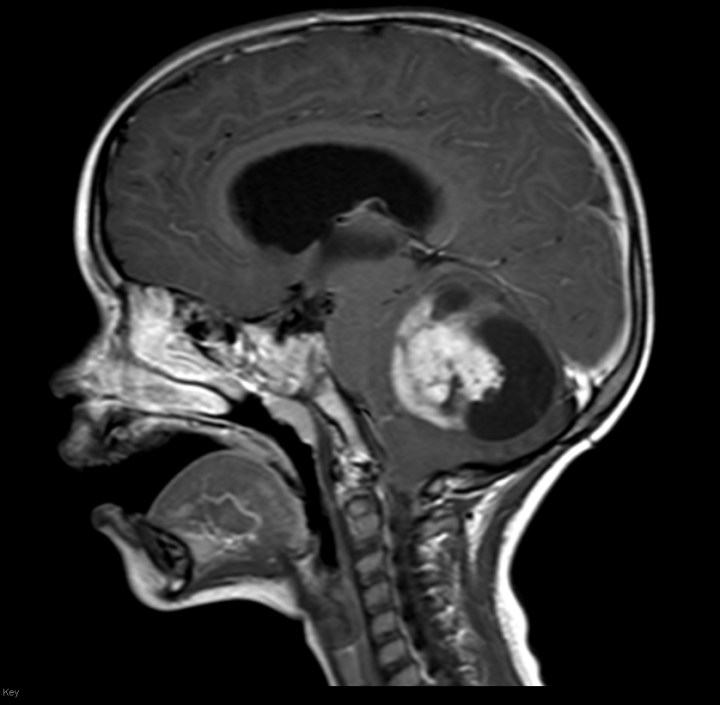

Astrocytomas are the most common type of glioma and contain the most detrimental subtype of brain cancers, glioblastoma multiforme. Astrocytomas affect the astrocytes in the brain, which make up the blood-brain barrier. Xia et al. from Purdue University looked to study the effect of SUMO-specific protease 1 (SENP1) knockout in cell lines derived from astrocytoma patients.

- Image retrieved from: https://pedclerk.bsd.uchicago.edu/page/childhood-astrocytomas